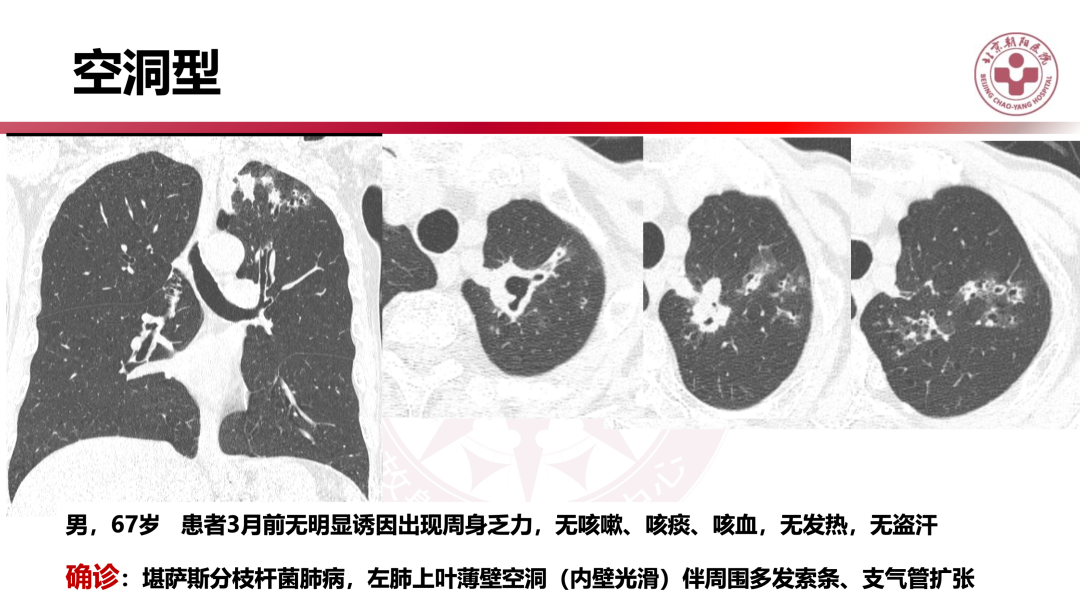

非结核分枝杆菌肺病有何影像学特点?|影像读片

来源 北京朝阳医院放射介入中心

课件提供 张子豪 翟晓力(放射)

点评专家 陈宁(放射)